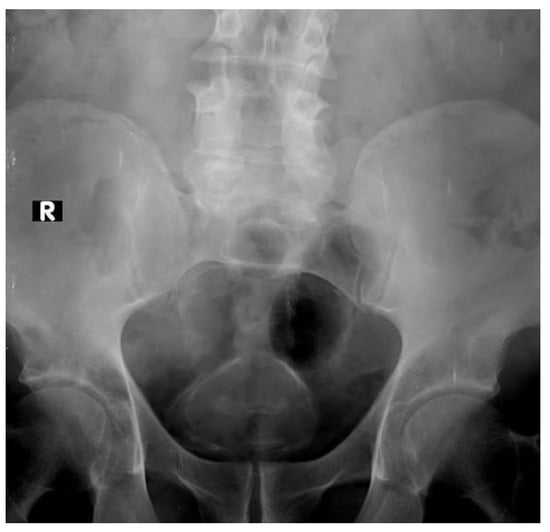

2.1. Plain X-ray

- Pollack, H.M.; Banner, M.P.; Martinez, L.O.; Hodson, C.J. Diagnostic considerations in urinary bladder wall calcification. AJR Am. J. Roentgenol. 1981, 136, 791–797. [Google Scholar] [CrossRef]